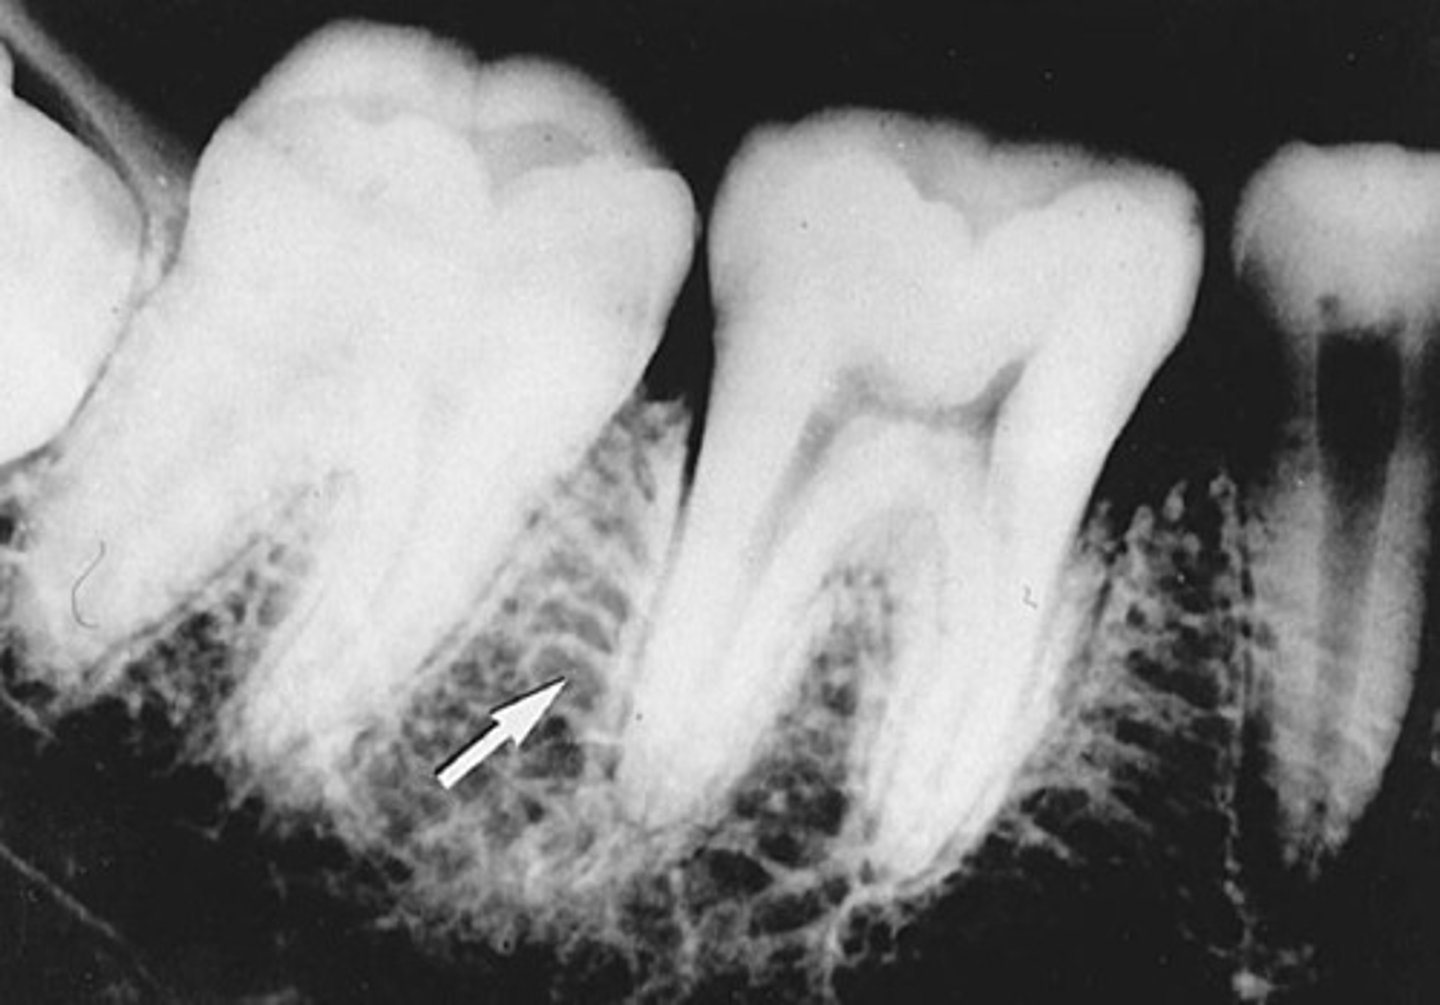

Nutrient canals

What is the radiolucent structure seen here?